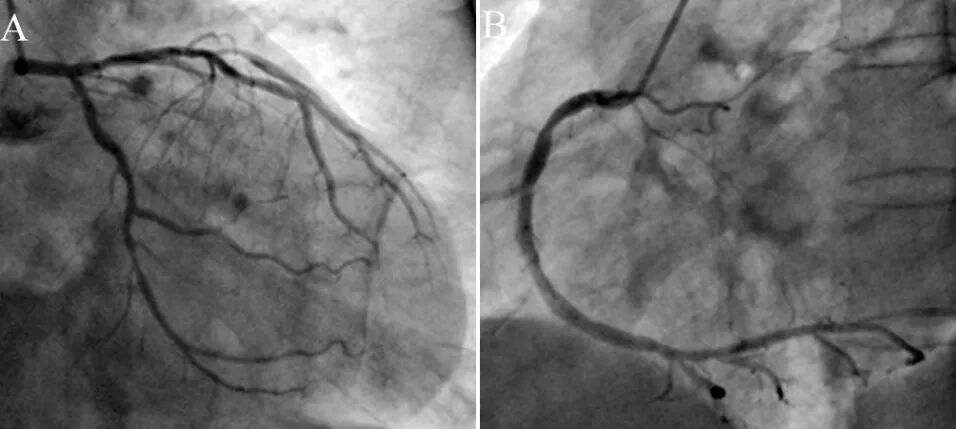

2、冠脉造影

次日行冠状动脉造影提示三支临界性病变(图9)。左主干狭窄30%~40%;前降支弥漫性病变,近中段狭窄50%,第一对角支狭窄50%;回旋支开口狭窄60%,中段狭窄40%;右冠弥漫性病变,中段狭窄最重40%;后降支开口狭窄狭窄70%。造影难以判断痉挛部位,故未予支架置入。拟次日进行科内讨论药物治疗方案,并进一步评估安装起搏器或埋藏式心脏复律除颤器(ICD)的必要性和可行性。

图9 冠脉造影